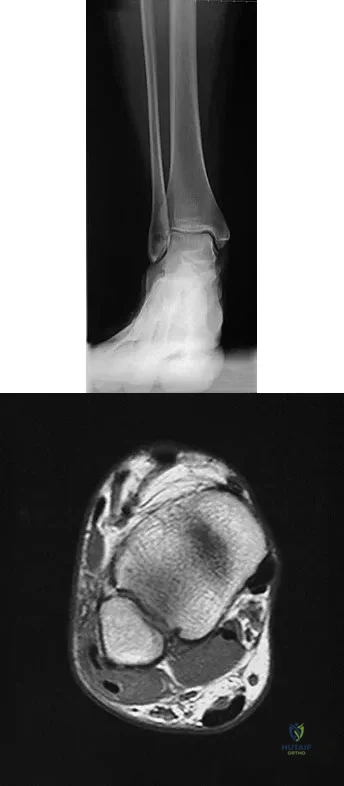

Question 69

A 25-year-old competitive skier sustains a twisting injury to the right ankle while skiing. She is unable to continue the activity secondary to severe lateral ankle pain. Examination reveals ecchymosis and fullness over the lateral malleolus with pain and weakness on active ankle dorsiflexion and external rotation. There is no medial-sided pain. Neurovascular examination is normal. An AP radiograph and MRI scan are shown in Figures 17a and 17b, respectively. Management should consist of

Explanation